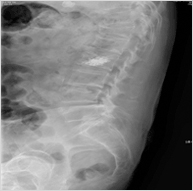

척추압박골절 - 사진

척추압박골절

정의

뼈속의 칼슘이 빠지면서 척추뼈가 약해져 가벼운 충격(삐끗하거나 넘어질 경우)으로도 척추뼈가 눌리는 골절이 발생 할 수 있다.

증상

심한 요통과 압통으로 눕거나 일어날 때 심하게 통증을 호소하며 골절된 부위를 가볍게 두드려도 통증을 호소한다.

원인

골다공증으로 약해진 척추뼈가 충격에 의해 손상.

치료

대개의 경우 보존적인 약물치료나 물리치료 등으로 통증을 완화시킬 수 있으며 이러한 치료 에도 효과가 없을 경우 보다 적극적인치료를 해볼 수도 있다. 디스크 열치료술이나 내시경적 수핵성형술 등의 치료를 시행할 수도 있다.